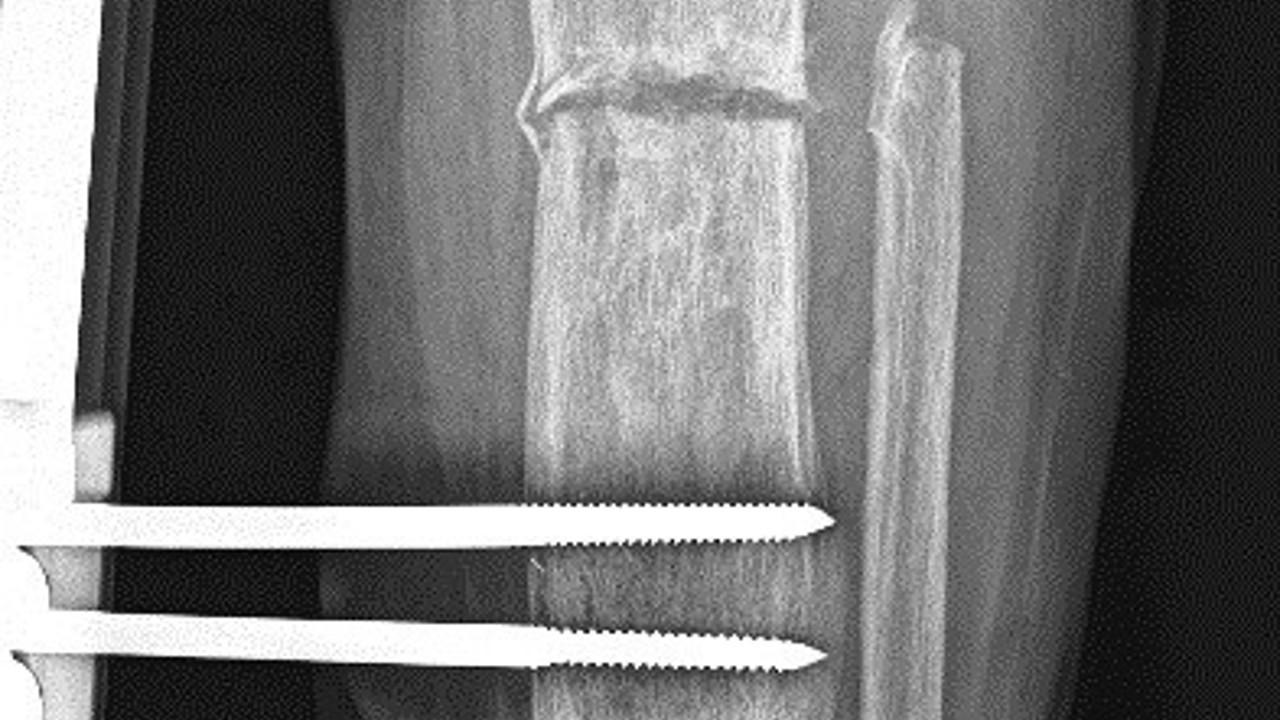

Ortopedi servisinde Ortopedist Op. Dr. Ali Canbay ve Op. Dr. Serdar Karaman tarafından tetkikleri yapılan hastaya, boy (kemik) uzatma operasyonu yapılması kararlaştırıldığı vurgulandı. Hastanın bacağına, ilk ameliyatında kısa olan kemiği günde 1 mm uzatma olacak şekilde bir sistem kuruldu. Başarılı geçen operasyon sonrasında kurulan sistem sayesinde 5 cm uzama ve yıllardır kaynamayan kemikte kaynama elde edildi. Son olarak dışarıdan uygulanan bu sistem çıkarıldı ve uzamanın kontrol altına alınması için çivi denilen işlem uygulandı. Hasta, tüm bu işlemlerin akabinde aksamadan yürümeye başlayarak eski sağlığına kavuştu.

Operasyonla ilgili Elbistan Devlet Hastanesi''nden yapılan açıklamada; “İş kazası nedeniyle beş yıl önce kaval kemiğinde parçalı kırığı olan ve kırık olan bacağında diğer bacağına kıyasla kısalığı devam eden hastamıza, Elbistan Devlet Hastanesi’nde Ortopedist Op. Dr. Ali Canbay ve Op. Dr. Serdar Karaman’ın birlikte yaptıkları iki operasyon sonucu hasta eski sağlığına kavuşmuştur. İlk ameliyatında kısa olan kemiği günde bir milimetre uzatma olacak şekilde kurulan sistem ile 5 cm uzama ve yıllardır bir türlü kaynamayan kemikte kaynama elde edilmiştir. Son olarak dışarıdan uygulanan sistem çıkarılıp hastanın konforlu hayatına dönmesi için çivi denilen işlem ile mevcut uzamanın koruma altına alınıp hastanın tekrar aksamadan yürümesi sağlanmıştır” ifadeleri kullanıldı.